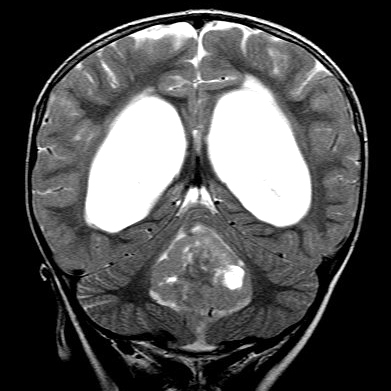

![]() Ependymoma of the 4th ventricle and hydrocephalus. |

Ependymomas are predominantly tumors of children and adolescents. They arise most frequently in the fourth ventricle and cause hydrocephalus by blocking CSF flow. However, they may occur anywhere in relation to the ventricular system or central canal of the spinal cord and are the most common primary intra-axial tumors in the spinal cord and filum terminale. Ependymomas are well demarcated from the surrounding brain and grow in an exophytic fashion, protruding into and out of the fourth ventricle. Spinal ependymomas are circumscribed intra-axial masses. Some supratentorial ependymomas are exraventricular and may be cystic.